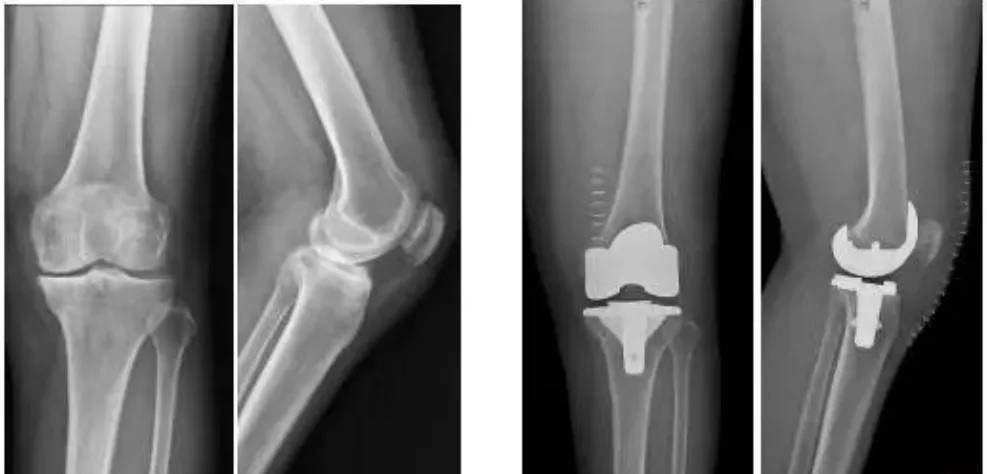

9月30日,四川大學(xué)華西醫(yī)院骨科的周宗科教授團(tuán)隊成功為患有膝關(guān)節(jié)骨關(guān)節(jié)炎的吳婆婆植入了3D打印分區(qū)骨小梁生物型膝關(guān)節(jié)假體。飽受膝關(guān)節(jié)疼痛折磨多年的她,在接受手術(shù)20多天后,恢復(fù)了正常的行走能力。

這種新型假體與傳統(tǒng)骨水泥假體相比,其通過假體—骨界面緊密接觸,促使骨組織長入假體,提高假體與髓腔的結(jié)合強(qiáng)度,從而達(dá)到假體的長期穩(wěn)定。使用生物型人工膝關(guān)節(jié),可保存患者骨量,同時避免或降低了骨水泥所導(dǎo)致的毒副作用。

全球首款3D打印,分區(qū)骨小梁生物型膝關(guān)節(jié)假體

膝關(guān)節(jié)骨關(guān)節(jié)炎是一種退行性疾病,近年隨著經(jīng)濟(jì)發(fā)展和人口老齡化趨勢日趨明顯,尤其是在中老年群體發(fā)病率較高,因此膝關(guān)節(jié)置換術(shù)需求量日益增長。此外,隨著居民生活水平的提高,大多患者對于膝關(guān)節(jié)置換術(shù)術(shù)后的生活質(zhì)量和植入假體有了更高的要求,隨之假體在設(shè)計和創(chuàng)新方面也更精準(zhǔn)、更便捷化。全球首款3D打印分區(qū)骨小梁生物型膝關(guān)節(jié)假體正是在這種高需求與高期待的新形勢下應(yīng)運(yùn)而生。

本次植入的生物型膝關(guān)節(jié)假體在術(shù)中無需使用骨水泥,通過機(jī)械方式進(jìn)行固定,即假體與骨組織的緊密結(jié)合,獲得假體的初始穩(wěn)定性,遠(yuǎn)期骨組織長入假體表面的微孔內(nèi)部,實現(xiàn)由機(jī)械固定向生物內(nèi)鎖固定的轉(zhuǎn)化,最終經(jīng)過骨整合作用獲得良好固定,預(yù)期能夠獲得更長的假體壽命。

周宗科教授介紹說,該款3D打印分區(qū)骨小梁生物型膝關(guān)節(jié)假體有三個亮點,一是脛骨平臺假體采用了3D打印骨小梁分區(qū)技術(shù),三分區(qū)設(shè)計使宿主骨均勻骨長入,避免因應(yīng)力分布不均而造成平臺假體松動等問題;二是所用股骨髁假體表面為真空等離子噴涂純鈦涂層,其粗糙的接觸面增加了骨誘導(dǎo)的能力,具有優(yōu)異的即刻穩(wěn)定和長期穩(wěn)定性;三是所用平臺墊為添加維生素E的高交聯(lián)超高分子量聚乙烯材質(zhì),具有優(yōu)異的耐磨性能。